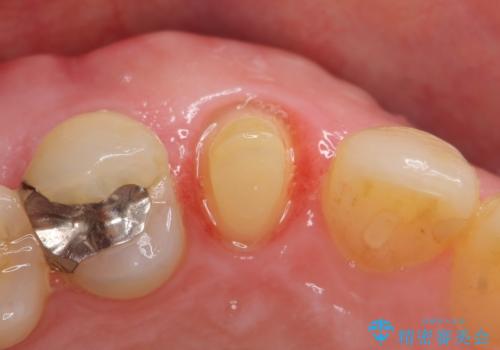

- 他院にて根管治療を行ったが疼きが治まらないため、当院にいらっしゃった方の症例です。

再根管治療を行い症状が治まったのを確認後、オールセラミッククラウン(スペシャル)による補綴を行いました。